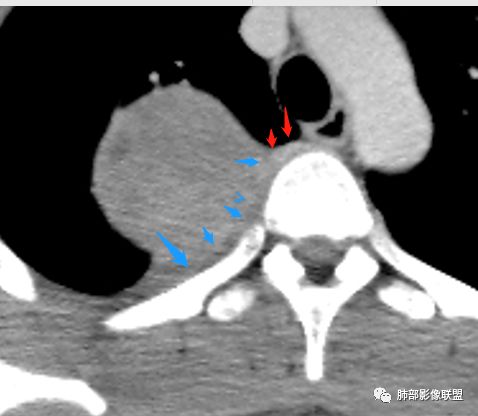

右后纵膈脊柱旁软组织占位,形态规则类圆,边缘光整,肺组织受压,胸膜尾,肋间动脉供血。中度不均匀延迟强化。

后纵隔脊柱旁占位性病变,疾病谱有神经鞘瘤,sft,节细胞瘤,髓外造血。此例有胸膜尾征,蛇纹征 ,延迟强化。考虑胸膜孤立性纤维瘤。看到有供血动脉,但不知道是哪里的血管。

后纵隔类圆形新生物,边缘光滑,胸膜尾征明显,贴近脊柱,蛇纹,血供丰富,考虑后纵隔软组织肿瘤,具体类型看不出来,鉴别神经鞘瘤。

右后纵膈脊柱旁软组织占位,边界清晰,光整,肺组织受压。胸膜被掀起,肋间动脉供血,中度不均匀延迟强化。考虑神经鞘瘤,不除外纤维瘤

右后纵膈脊柱旁软组织影,与纵隔结构分界不清,形态规则类圆,边缘光整,肺组织受压,胸膜尾,肋间动脉供血。肺动脉推移,中度不均匀延迟强化。考虑神经来源,神经鞘瘤,神经纤维瘤二者不易鉴别。

青年男性,间断胸痛;右侧脊柱旁可见一类圆形软组织密度影,密度欠均匀,增强扫描呈轻中度持续强化,邻近肺组织及肺动脉推移,可见肋间动脉供血,部分胸膜下脂肪可见,部分层面似见与右侧椎间孔相连。考虑后纵隔神经源性肿瘤。

边缘光滑,宽基底与胸壁相连,跨叶裂,叶裂稍前推,血管、支气管前移。

浅分叶

外上侧少量胸水

肋间动脉供血,强化尚均匀,逐步强化

1.右上胸内脊柱旁类圆形肿块,质地似乎比较坚实,密度稍显不均,但未显示明确的坏死。

如此密度形态的病灶位于肺边缘首先应当想到孤立性纤维瘤,可相邻胸膜未见明显的异常强化和胸膜方向延伸。

注意所谓“胸膜尾征”的概念及形成机制与“脑膜尾征”是大不相同的。

2.肋间动脉病供血也提示肿块来自后纵隔?

3.相邻椎间孔未见扩大,也未见块影延入椎管,易起自于神经根的鞘瘤似乎找不到支持点。

可惜未提供矢状位骨窗图像,如在肋骨内下缘观察到压迹有助于肋间神经的鞘瘤的判断,这是因为二者之间密切的毗邻关系。

4.静脉期轻度不均匀强化,注意不是环形强化,亦未见明确的“AB区”,这点也不支持神经鞘瘤。临床及病灶轻度强化都不支持副节瘤。

尽管神经纤维瘤的诊断确实有些出乎意外,但病例开阔了我们的视野。